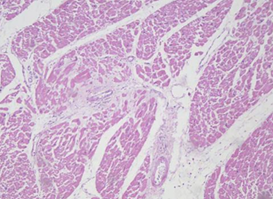

四、 HE染色

苏木精-伊红染色法 ( hematoxylin-eosin staining ) ,简称HE染色法 ,石蜡切片技术里常用的染色法之一 。苏木精染液为碱性 ,主要使细胞核内的染色质与胞质内的核糖体着紫蓝色 ;伊红为酸性染料 ,主要使细胞质和细胞外基质中的成分着红色 。HE染色法是组织学、胚胎学、病理学教学与科研中最基本、使用最广泛的技术方法。